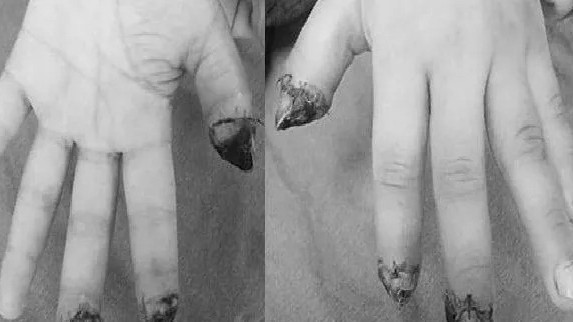

Dù không gây đau, khối u này ngày càng lớn dần. Qua thăm khám và xét nghiệm, các bác sĩ chẩn đoán bệnh nhân mắc dị dạng thông động – tĩnh mạch (AVM). Đây là một bệnh lý mạch máu hiếm gặp, nhất là ở bàn tay.

| Bệnh nhân mắc dị dạng thông động – tĩnh mạch (AVM), một bệnh lý mạch máu hiếm gặp, nhất là ở bàn tay |

Trước đó, bệnh nhân đã đi khám ở nhiều nơi nhưng bị chẩn đoán nhầm là u phần mềm, u thần kinh hoặc bao gân do hình thái bên ngoài dễ gây hiểu lầm. Chỉ đến khi đến Bệnh viện Bệnh Nhiệt đới Trung ương, các bác sĩ mới phát hiện khối u chứa toàn các cuộn mạch máu đan chéo – dấu hiệu đặc trưng của AVM.